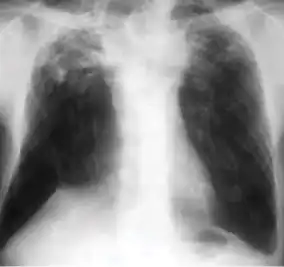

Dense homogenous opacity in right, middle and lower lobe of primary pulmonary TB. -